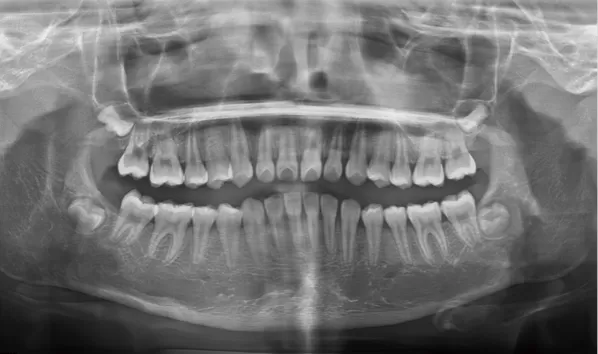

X-rays before treatment

[Panoramic Radiography/Lateral Cephalogram]